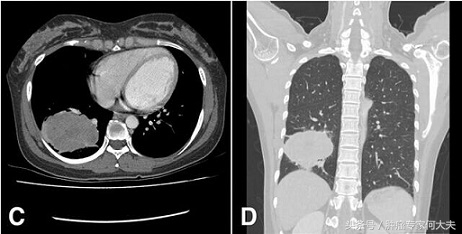

得了肺癌没钱治怎么办,家境贫寒如何选择肺癌晚期治疗 今日上午,接到一个咨询电话,病人老张家是江西农村的,男性,68岁,一月前因持续发热,被确诊为右肺腺癌,纵膈、肺门淋巴结转移,单侧胸腔积液。病人儿子小张在上海打工多年,因此就把父亲的病情资料带到上海市多家医院咨询治疗方案,大致意见就是建议住院,做全身PET-CT,若无远处转移,先新辅助化疗,再考虑可否手术,同时建议进行基因检测,这一系列下来差不多得十万左右。小张告诉我说,他问上海医生,他花这么多钱,能彻底治好吗?医生说不一定!于是,小张就慌了神。到底这个钱花不花?